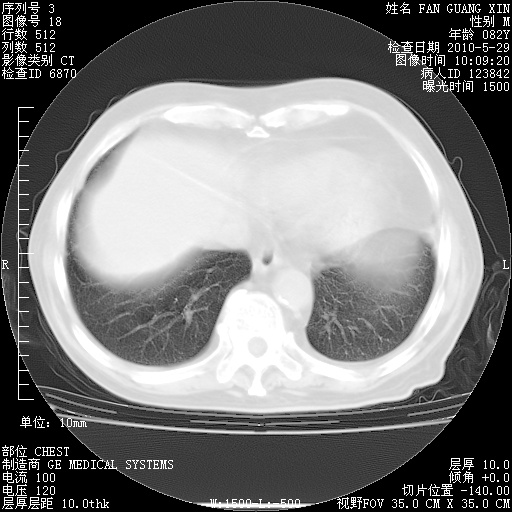

还需要哪些辅助检查?我们医院排除真菌感染没有任何检验方法,胸片好像能够排除肺部真菌感染。